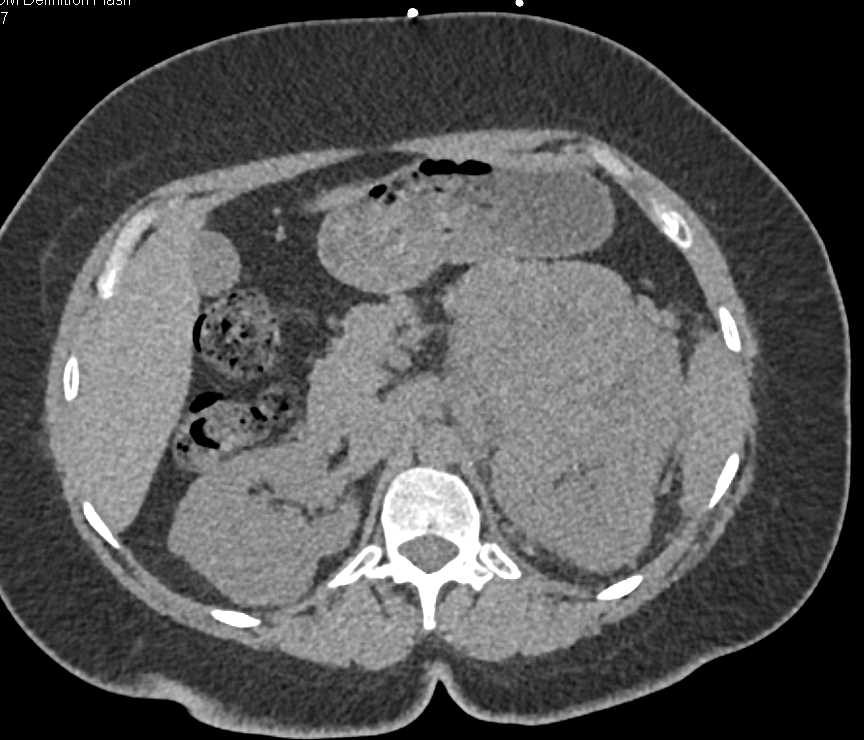

Renal Cell Carcinoma Metastatic to the Left 12th Rib